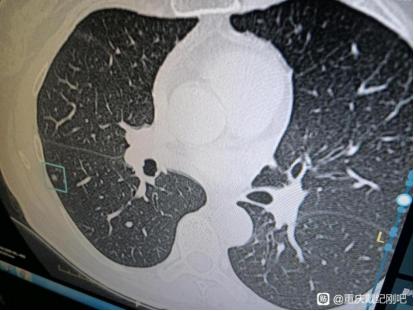

今天这位患者的情况是比较特殊,因为她的四个混合性磨玻璃结节其实都比较小,最大才5mm。但是四个结节术后大病理却都已经是微浸润腺癌了,复查三次当地医院都说还小,不用管他。患者找到我面诊之后,我当即判断可能已经是微浸润腺癌了,但再随访一段时间可能也是安全的。患者心理压力非常大,无法安心随访。患者很信任我,说把医保都已经提前迁到了重庆,但是其实像这种结节越小,越不好手术,很容易漏诊漏切,很容易在手术中就根本找不到目标结节,切掉的是疑是结节而漏掉目标结节。但在我这里,这些难题都是可以“手拿把攥”的,把只要有危险的肺结节一网打尽,才是我的风格。

在给爸爸陪床期间,我也做了肺CT,显示有小结节。医生叮嘱我,三个月复查就可以。复查了3次后,医生都说芝麻大小的结节,不用管它。在新桥医院做的高分辨CT,有4个结节。

这4个小的混合性磨玻璃结节,最大0.5cm,最小0.3cm,在当地医院,手术只能切除最大的。那么,留下任意一个,都将是致命的。看了混磨再小,也不能掉以轻心。